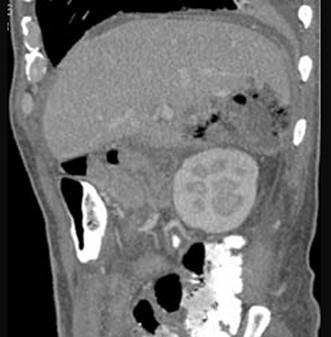

问题 男,44岁,发热、右上腹痛、压痛,右下肺呼吸音低,影像检查如图,最佳诊断是 ( )

选项 A、肝硬化腹水 B、肝癌 C、膈下脓肿 D、肝包膜下出血 E、腹腔积液

答案 C